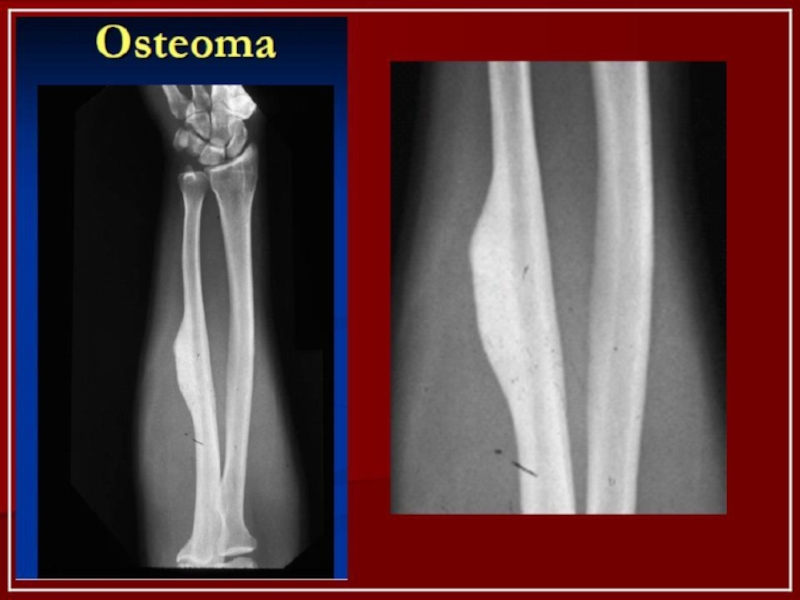

Слайд 18Остеома

Остеома – опухоль из относительно зрелой костной ткани. Встречается редко.

Выделяют:

1)компактные

(характеризуются отсутствием каналов остеонов и узкими сосудистыми каналами);

2)губчатые (имеет порозное

строение);

3)мягкие (отличаются большим количеством костномозговых полостей) остеомы.

Остеомы могут иметь центральное и периферическое расположение.

Остеомы растут очень медленно. Жалобы больных зависят от локализации и объема опухоли: развившись в толще нижней челюсти, она вызывает невралгическую боль в области нижнеальвеолярного нерва и асимметрию нижней половины лица, при локализации на венечном отростке, вызывает постепенно нарастающее ограничение движений нижней челюсти, прорастая в полость носа – затрудняет дыхание через соответствующую половину носа.

Малые остеомы обычно не причиняют никаких функциональных или косметических расстройств.